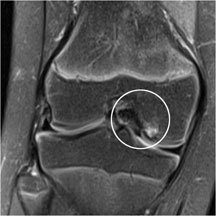

The MRI on the left is showing the lesion from a different angle and with a different contrast. The fragment was stable on the MRI, so I treated her non-operatively for 4 months on crutches hoping it would settle. Unfortunately, it didn't, so I took her back to the operating theatre (OR) in November.